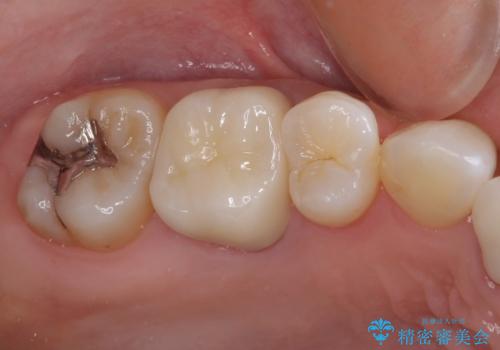

他院で矯正治療をされていたそうですが、矯正治療前から変色は気になっており、歯並びが整ってからは、より気になるようになっていたそうです。

自然に仕上がり、患者様には大変満足していただきました。